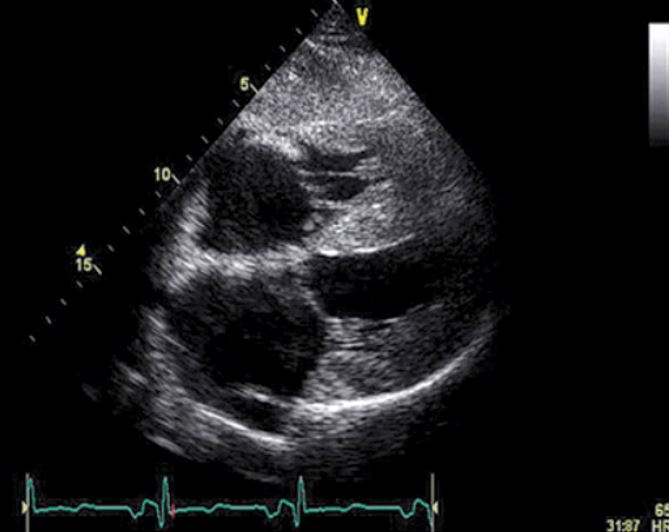

This is the most likely diagnosis for a patient with a low voltage EKG and these imaging findings.

What is cardiac amyloidosis.